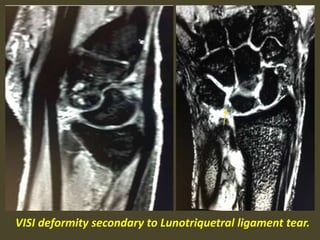

Volar intercalated segmental instability(VISI).

VISI with volar tilting of the lunate.

VISI with luno-triquetrum ligament tear and volar tilting of the lunate.

VISI deformity secondary to Lunotriquetral ligament tear.